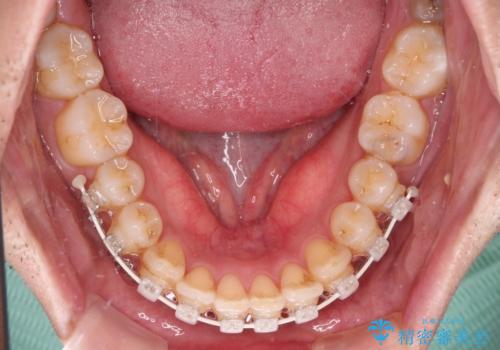

- 矯正装置

- 審美装置

- 治療期間

- 1年

- 治療回数

- 10-30回